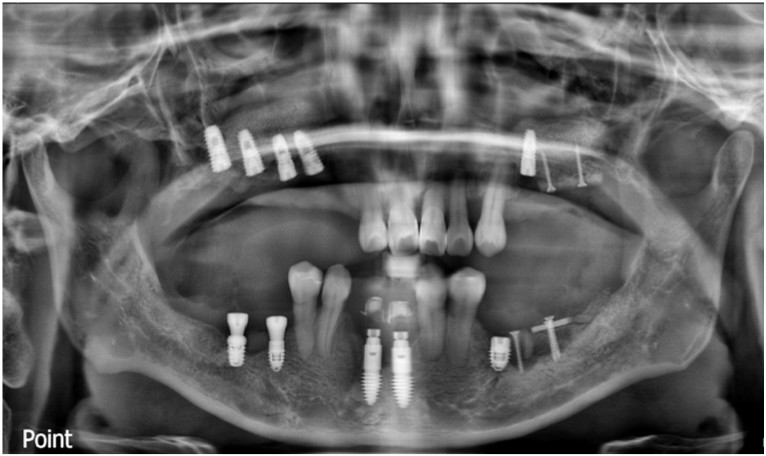

먼저 예후가 좋지 않은 치아들과

타 치과에서 식립 해 둔

아래턱 앞니 임플란트를

모두 제거하였으며,

아래턱 오른쪽 어금니 부위와

앞니에 먼저 임플란트 식립을

도와드렸는데요.

정확한 위치에

안정적으로 임플란트가 식립 된 것을

확인할 수 있었으며

한 달 반 뒤

아래턱 오른쪽 작은 어금니 부위에

임플란트 식립을 도와드렸으며,

큰 어금니 부위에는

잔존 잇몸뼈의 소실이 심한 상태라

바로 임플란트 식립을 진행하지 못하고

뼈이식을 도와드렸는데요.